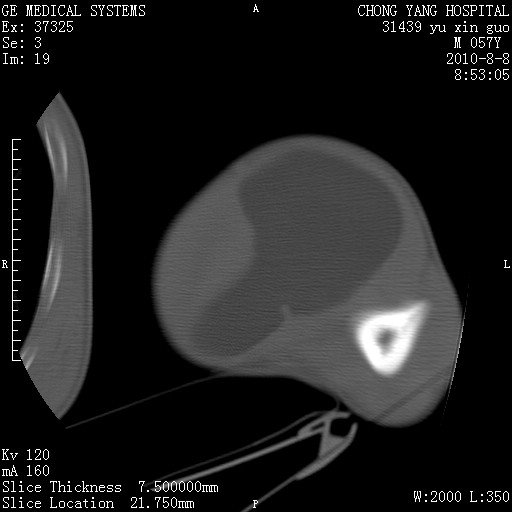

标题: CT28267:M57Y 上臂包块8年余。 [打印本页]

标题: CT28267:M57Y 上臂包块8年余。

包膜光滑、完整的脂肪密度肿块,支持脂肪瘤。

脂肪瘤。有ct值?